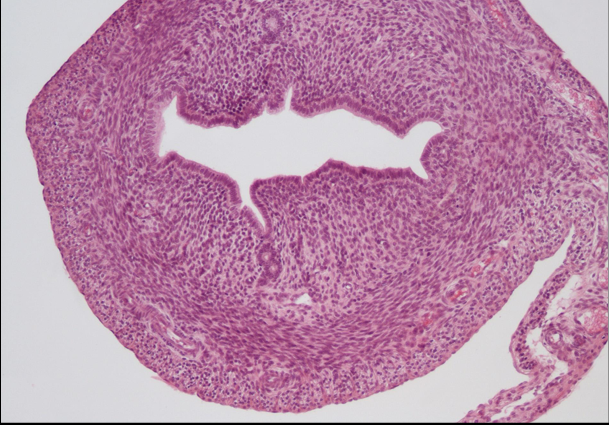

macica nr 413

nabłonek jednowarstwowy walcowaty urzęsiony - ściana macicy

blaszka właściwa

mięśniówka gładka

błona surowicza lub przydanka